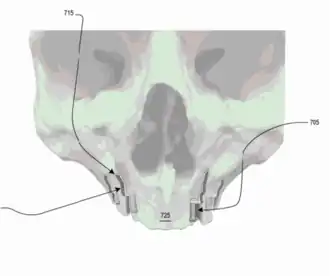

Hale has collaborated with the medical device manufacturer KLS Martin on the development of patient-specific surgical solutions for jaw deformities. Their work led to the creation of the KLS Martin PreProsthetic, which is the first FDA-approved device designed for the treatment of edentulous ridge deformities. The KLS Martin PreProsthetic Device represents a significant improvement over current implant technology, especially for patients with insufficient bone for conventional implant reconstruction.